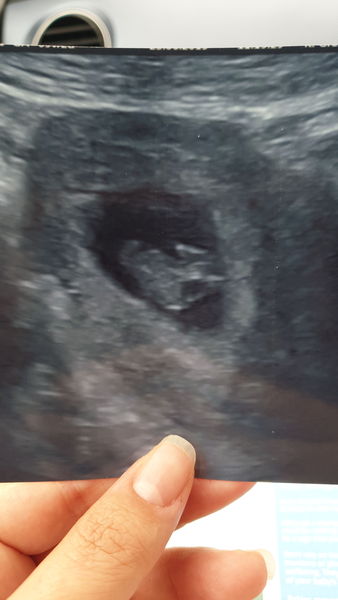

So many lovely scan pics, I had my private scan today, baby measured exactly 10 weeks which is what I am. Baby didn’t move though in the scan other than it’s heartbeat, I guess it was Sunday so a day of rest.